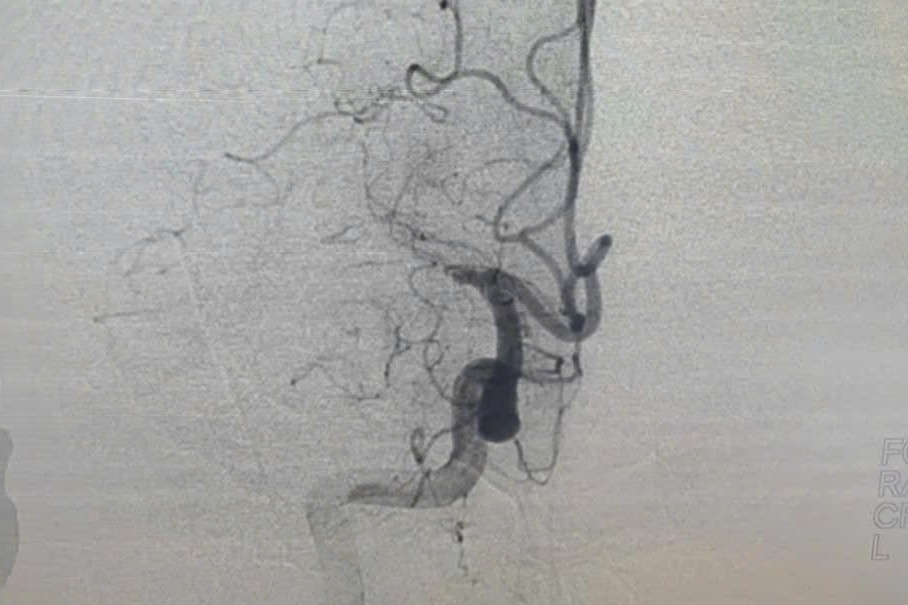

Nữ bệnh nhân 25 tuổi nhập viện trong tình trạng có vết thương sưng nề vùng thái dương trái do lưỡi kéo sắc nhọn găm sâu vào hộp sọ.